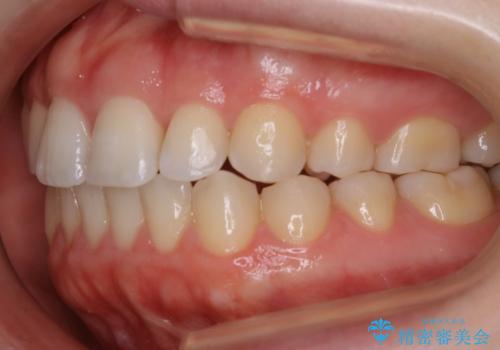

【非抜歯】上下の前歯が噛み合わないオープンバイトの治療

- 噛み合わせの不調を主訴にご来院されました。

骨格的な問題もあり、噛んだ時に奥歯しか当たらず前歯の被蓋があまりない状態でした。

奥歯を沈めて噛み込みを深くしていくことで被害の改善が起こるとともに、下顎自体が前上方に回転移動することで顔貌的にも変化を出すことができます。

臼歯の位置が高く噛んだ時に奥歯しか当たらなかったり、舌癖などが原因で前歯が前に倒れてしまうことで上下の前歯の被蓋がなくなってしまっている状態をオープンバイトといいます。

前者の場合は臼歯を圧下し沈めてあげることで改善させます。後者の場合は前方に傾斜している歯を元の角度に戻してあげることで改善しますが、舌癖がある場合はその癖自体を無くす治療をしない限りまた同じ状態へと後戻りしてしまいます。